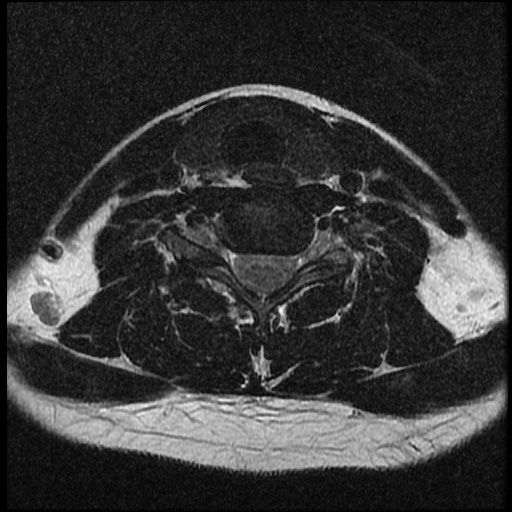

이 MRI 사진은 21년도 사고 당시 찍은 MRI 사진 입니다. 확인 부탁드립니다~

전체 mri를 다 봐여겠지만 보여주신 mri 컷에서는 의미있는 경추 디스크탈출이 보이지 않습니다.